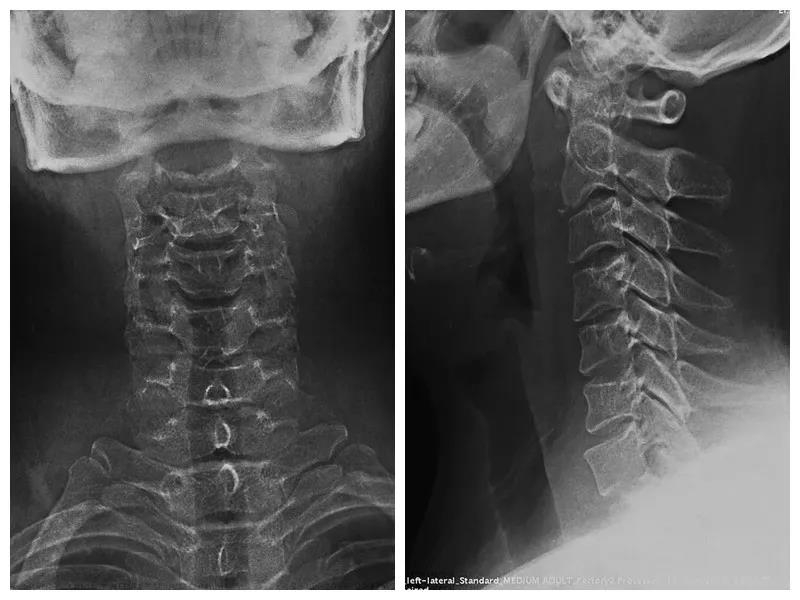

术前X线正、侧位片

术后X线正、侧位片